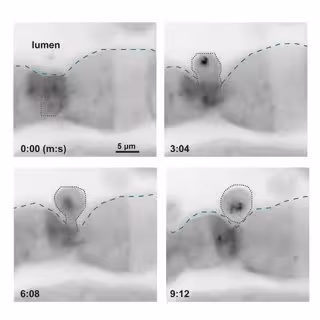

En esta serie (de izquierda a derecha desde arriba a la izquierda), las células epiteliales de un pez cebra expulsan en menos de diez minutos una célula compañera que ha sido marcada para su eliminación debido a una exposición química.

En esta serie (de izquierda a derecha desde arriba a la izquierda), las células epiteliales de un pez cebra expulsan en menos de diez minutos una célula compañera que ha sido marcada para su eliminación debido a una exposición química. - JOHN RAWLS LAB, DUKE UNIVERSITY

El revestimiento del intestino es una sola capa de células epiteliales similares a los dedos que se encuentran muy juntas. Cuando una célula epitelial intestinal está alterada, de alguna manera se marca para su destrucción. Durante la delaminación, las células epiteliales vecinas empujan contra la célula 'condenada' hasta que la expulsan. "No esperábamos que la delaminación fuera protectora", reflexiona Espenschied.